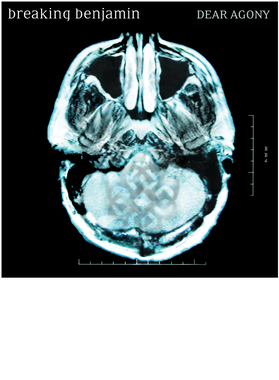

Upgrade your wardrobe with the best-selling **Agony Unisex Cotton Tee Classic T Shirt graphic tee**. Made from **100% combed and ring-spun cotton**, this shirt is designed for **ultimate comfort, breathability, and long-lasting durability**. Featuring **high-quality digital print technology**, the vibrant artwork is bold, clear, and **resistant to fading**, even after repeated washes.

- High-Quality Digital Print: Crisp, high-resolution design that stays sharp after many washes.

Upgrade your wardrobe with the best-selling **Agony Unisex Cotton Tee Classic T Shirt graphic tee**. Made from **100% combed and ring-spun cotton**, this shirt is designed for **ultimate comfort, breathability, and long-lasting durability**. Featuring **high-quality digital print technology**, the vibrant artwork is bold, clear, and **resistant to fading**, even after repeated washes.

- High-Quality Digital Print: Crisp, high-resolution design that stays sharp after many washes.